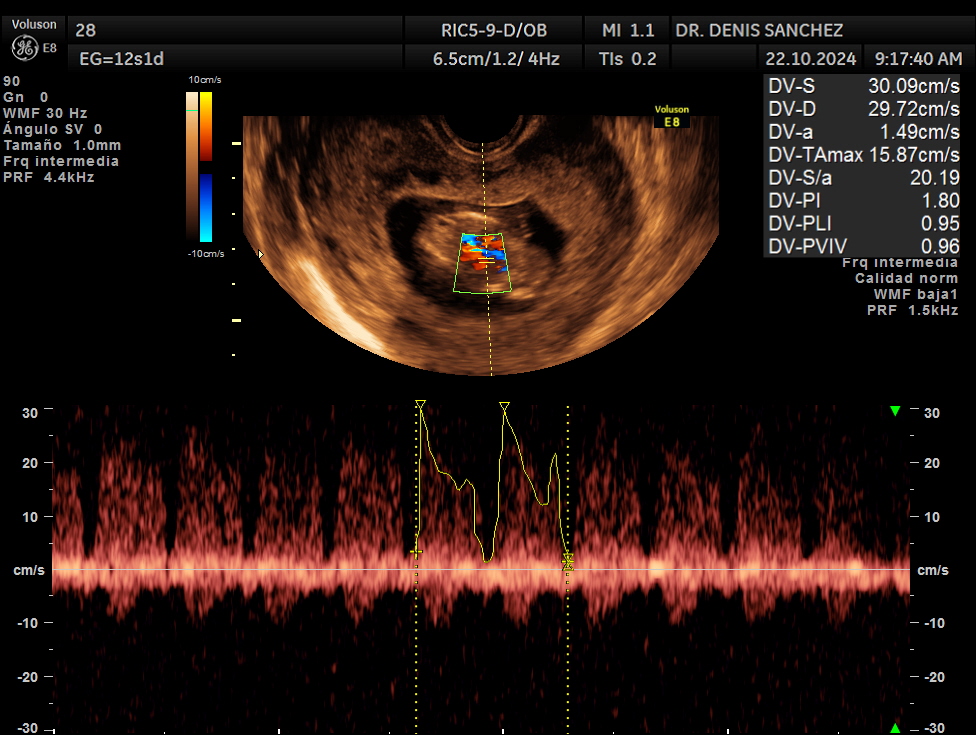

Flujo en el ductus venoso: se estudia mediante Doppler color.

Cada examen se complementa con un análisis estadístico personalizado, que calcula la probabilidad de riesgo según los parámetros ecográficos obtenidos.

Este informe cuantitativo ayuda a orientar la evaluación médica y las decisiones posteriores.